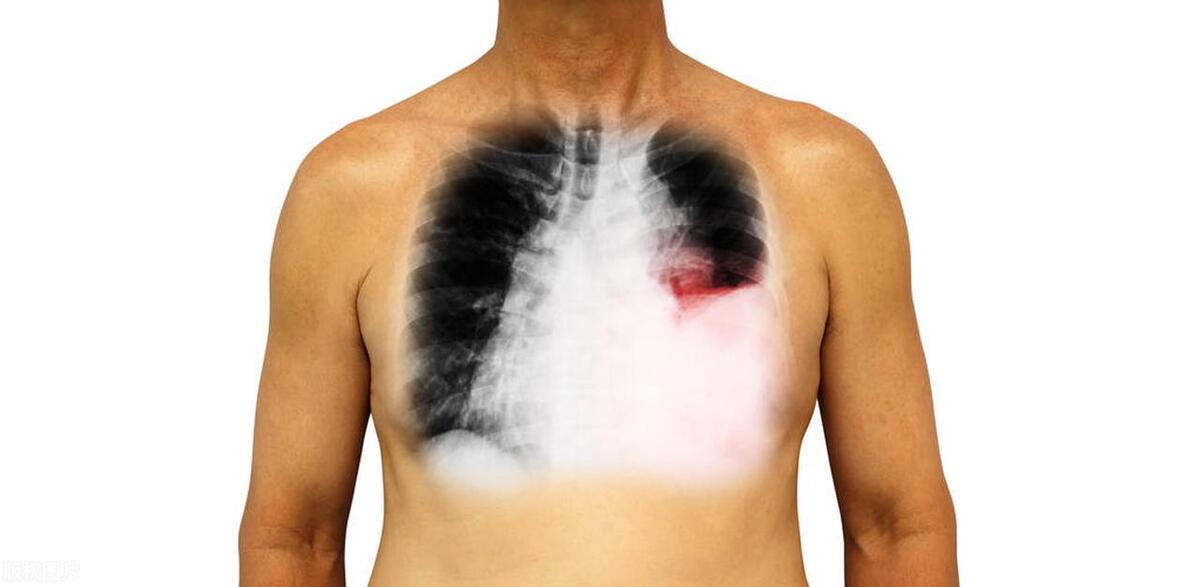

2、肺部炎症是肺部组织感染或炎症引起的疾病,其中包括肺炎和支气管肺炎。这些疾病会导致肺部疼痛、咳嗽、胸闷等症状。肺炎常见的病因包括病毒、细菌和真菌感染,这些病原体侵入肺部,引发炎症反应,损伤肺组织并导致疼痛。

4、胸膜炎是指胸膜的感染或炎症,胸膜是覆盖在肺部和胸腔内壁的薄膜。胸膜炎常由病毒感染、细菌感染、肺部感染或肺血栓栓塞症等引起。炎症引发胸膜间隙的渗出液增加,导致胸腔内压力增加,进而引起胸痛和呼吸困难。胸膜炎的症状通常在吸气和呼气时加重,因为这会导致胸膜的摩擦。